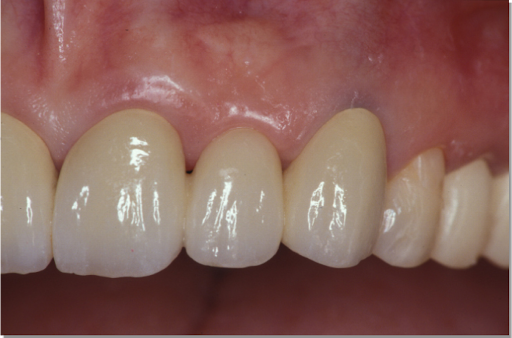

| 主訴 | 全顎治療希望、下の奥の歯が無いので全く噛めない。綺麗で噛めるようになりたい |

| 治療内容 | 下顎臼歯部欠損放置のため、臼歯部においてスペースがないため、全顎治療を行い咬合再構成を行う。 早期においてインプラント治療、咬合関係を模索した後、全顎にわたりセラミックによる補綴治療、その後メインテナンスに移行 |

| 治療費 | 5,410,000円(税込)(インプラントすべて含む) |

| 治療期間 | 1年8ヶ月 |

| 治療回数 | 80回 |

| 想定されたリスク | 食いしばり(パラファンクション)によるセラミックの破折、歯の破折 |